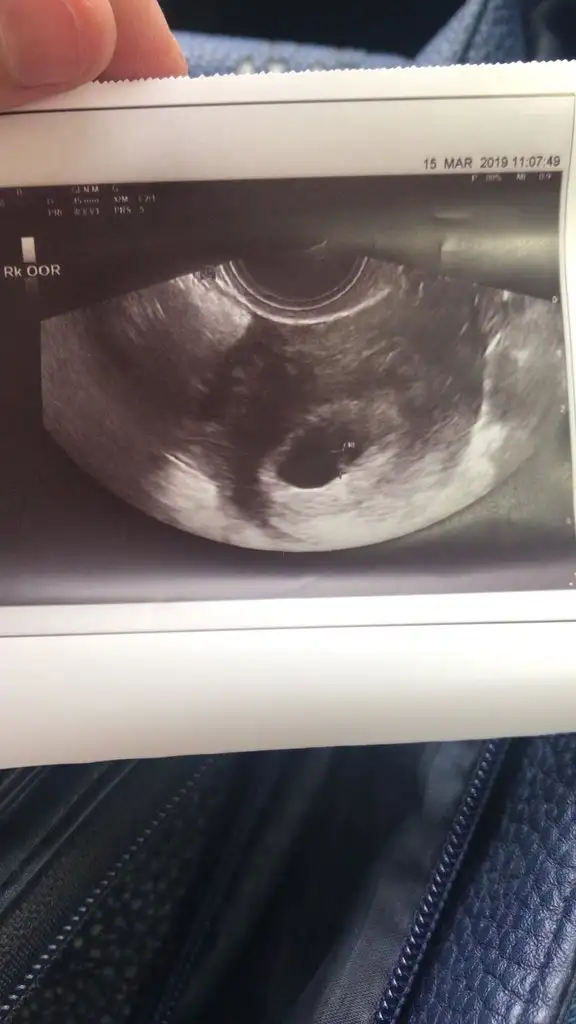

bizede yorum yaparmısınız 7+3Erkek tahminimce.

Erkek büyük ihtimal canımbizede yorum yaparmısınız 7+3